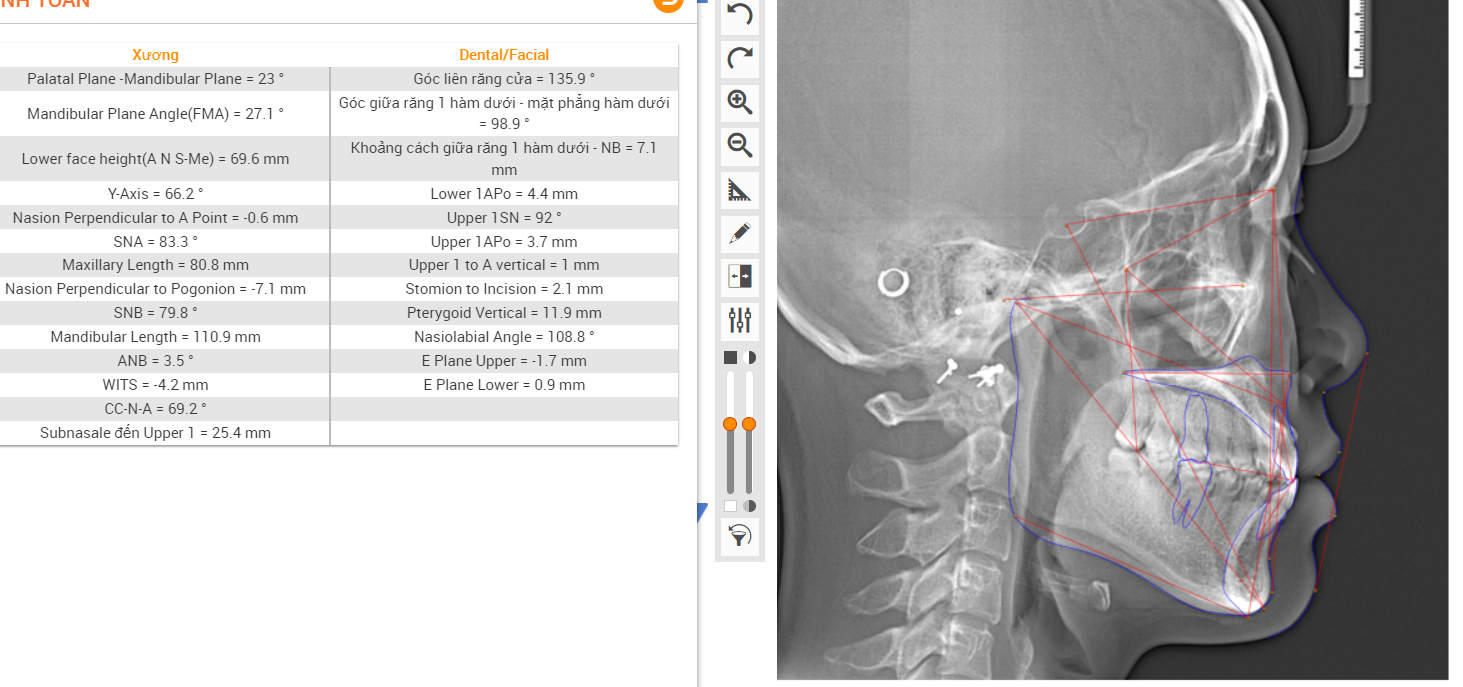

X-Matrix ứng dụng SmileStream trong việc phân tích phim và lên kế hoạch điều trị

Để khắc phục nhược điểm của công nghệ cũ, niềng răng X-Matrix ứng dụng các công nghệ hiện đại ngay từ bước thu thập dữ liệu để đảm bảo độ chính xác tuyệt đối:

- Chụp 3 loại phim: Cephalometric, Panorama và CT để khảo sát cấu trúc xương, tình trạng xương và các cấu trúc giải phẫu.

Bác sĩ sẽ phân tích và lên kế hoạch điều trị cho khách hàng đảm bảo các tiêu chí chính xác, an toàn và không đau với sự hỗ trợ của các phần mềm kỹ thuật số hiện đại:

- Phần mềm Autolign: đo đạc và mô phỏng hình dạng cung răng trong 3 chiều không gian, cá nhân hóa lựa chọn dây cung phù hợp nhất với tình trạng răng, lựa chọn hướng đặt mắc cài giúp răng di chuyển đúng vị trí 1 cách chuẩn xác, mô phỏng kết quả niềng răng chính xác tới 99,9%.

- Phần mềm SmileStream: tính toán chính xác lực di chuyển răng, tầm soát các nguy cơ biến chứng dựa trên dữ liệu từ 50 triệu ca niềng thành công khắp thế giới.

- Phần mềm WebCeph sẽ cho ra hình ảnh đa chiều, đa lớp cắt cho phép đánh giá toàn diện về cấu trúc của góc mũi môi, góc môi mềm trước và sau khi điều trị.